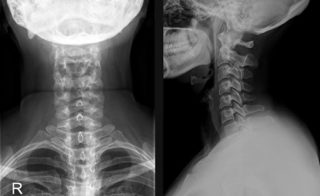

Рентген шей в 3 проекциях

Рентгенография в 2-х проекциях

Рентгенография в 3-х проекциях

Рентгенография в трёх проекциях дает возможность осуществить более качественную диагностику и обнаружить болезни на начальном этапе формирования. Больной поворачивается к кассете местами, на которые указывает рентгенолог.